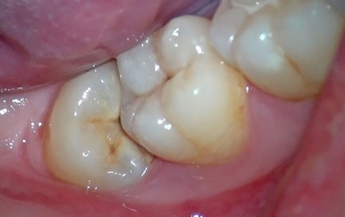

う蝕は進行度によって以下の図のようにC1~C4に分類され、それぞれ治療法が異なります。

• C1:エナメル質内のう蝕

歯の表面のエナメル質に限局したう蝕です。

ほとんど痛みなど自覚症状を伴わないことから、自ら気付かないことが多いため、歯科医院での定期的な検診により早期発見されることが重要となります。

• C2:象牙質に達するう蝕

エナメル質の内側の象牙質にまで達するう蝕です。

象牙質は歯の中の神経(歯髄組織)と関わっており、症状としては、冷たいものがしみたり、粘着性にある甘いもの(キャラメルやチョコレートなど)を食べると痛みが出たりします。

う蝕の範囲が狭い場合はう蝕を除去し、コンポジットレジン充填を行います。

範囲が広かったり、歯と歯の間(隣接面)にある場合は、う蝕除去後に歯型をとり、インレーと呼ばれる金属やセラミックの詰め物を作製し、修復します。